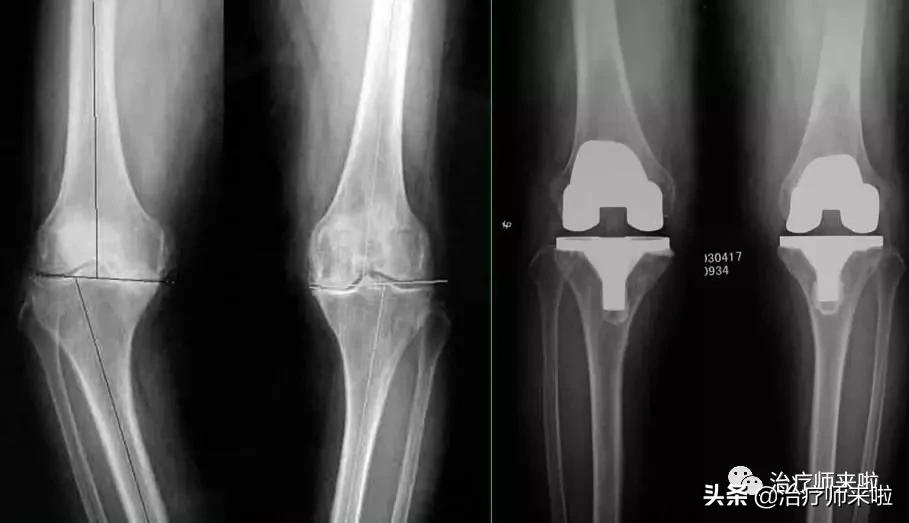

为了缓解疼痛、矫正畸形、稳定关节和改善关节功能,越来越多的患者会听从医生的建议选择置换人工膝关节。可是术后没有专业的康复训练,效果往往差强人意。那么问题来了,怎么样做到专业的康复?

1、手术情况,假体类型及屈曲限值。